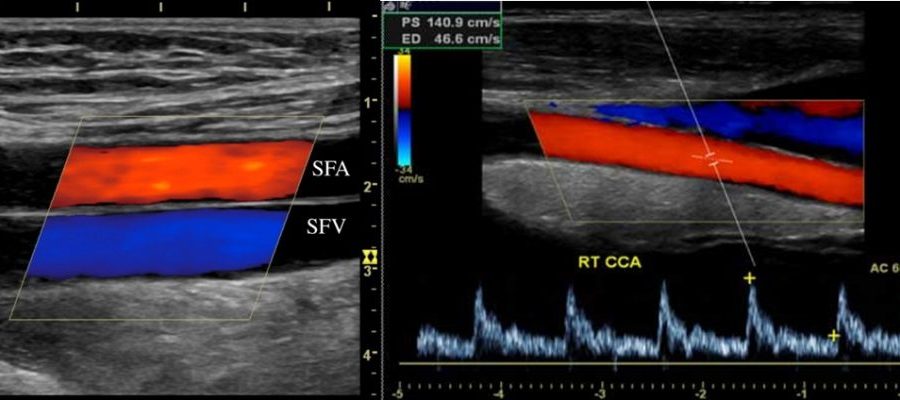

Когда к этому «двойному» режиму добавляется третий компонент - цветовое картирование кровотока (ЦДК), метод называют триплексным сканированием. На экране монитора потоки крови окрашиваются в разные цвета (традиционно красный - к датчику, синий - от датчика). Это не просто для красоты. Цветовое кодирование делает картину еще более наглядной и помогает врачу мгновенно выявлять проблемные зоны: участки турбулентного, завихренного кровотока за атеросклеротической бляшкой или «цветовые утечки» при несостоятельности клапанов.